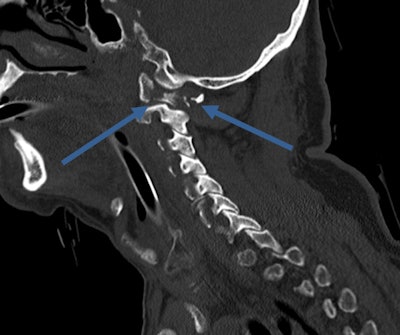

Because the population is aging, general radiologists are likely to come across geriatric trauma in regular routine practice. In the recent past, geriatric patients were often "underimaged," and the severity of injuries was likewise underestimated. Older people don't always complain even when they are in significant pain, explain trauma experts. Furthermore, mechanisms that would cause bruising in younger healthy adults, such as falling from a chair or from standing, can cause fractures and dislocations in geriatric patients.

"We often find numerous fractures from seemingly minor accidents. Despite a high scan rate in older patients, false-positive rates are low," noted Dick, who is also president of the British Society of Emergency Radiology.

Everyday life can be more risky: A 70-year-old fell down stairs, causing a fracture of C1 ring. Image courtesy of Dr. Elizabeth Dick.Besides maintaining a high index of suspicion in elderly trauma patients, a deep knowledge of their injuries and syndromes can help radiologists avoid errors: There may be degenerative changes in the spine, such as central cord syndrome (CCS), bruising of the cord caused by compression of the canal space, usually undetectable on CT and requiring MRI.